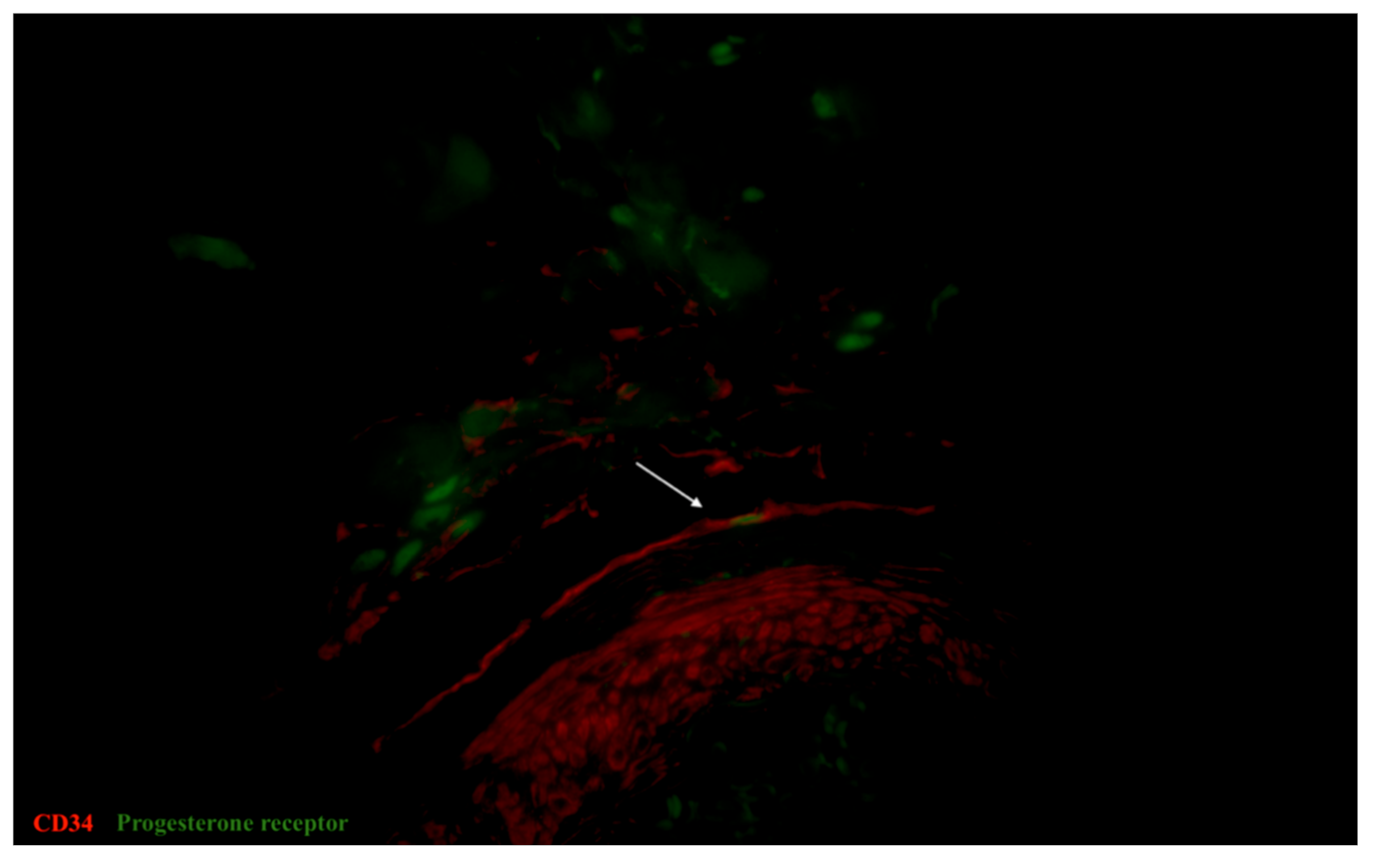

3.4. IHC Analysis of Estrogen and Progesterone Receptor Expression

- Cretoiu, S.M.; Cretoiu, D.; Suciu, L.; Popescu, L.M. Interstitial Cajal-like cells of human Fallopian tube express estrogen and progesterone receptors. J. Mol. Histol. 2009, 40, 387–394. [Google Scholar] [CrossRef]